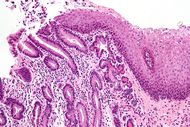

Micrograph of a gastro-esophageal junction with pancreatic acinar metaplasia. The esophageal mucosa (stratified squamous epithelium) is seen on the right. The gastric mucosa (simple columnar epithelium) is seen on the left. The metaplastic epithelial is at the junction (center of image) and has an intensely eosinophilic (bright pink) cytoplasm. H&E stain. | |